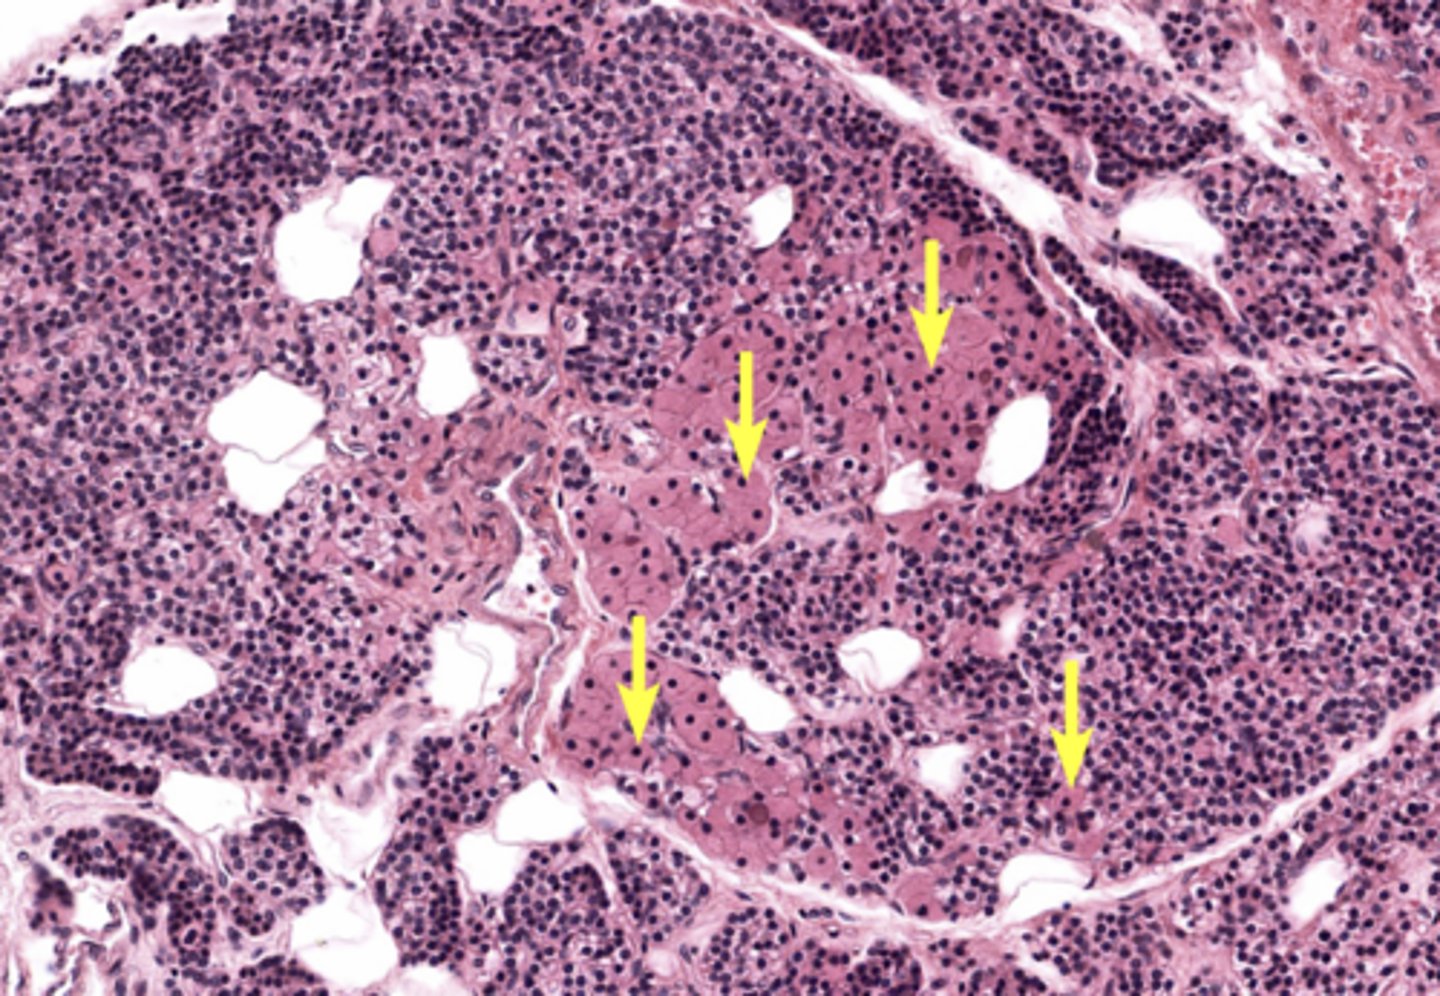

Pancreas

Pancreatic islet